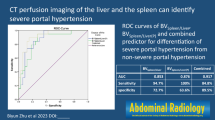

ROC analysis of SCL for differentiation between moderate and severe portal hypertension showed an area under the curve of 0.96 with a standard error of 0.04 (95% confidence interval (CI), 0.88–1) (Fig. 3). Using a cut-off value of 125 ml/min/100 ml for SCL, sensitivity for detection of severe portal hypertension was 94% with a specificity of 100%.

The Spearman correlation coefficient was −0.53 (p < 0.05) between SAF and HVPG, and −0.68 (p < 0.01) between HVPG and SCL. Using a cut-off value of 125 ml/min/100 ml for SCL, sensitivity for detection of a HVPG of ≥12 mmHg was 94%, and specificity 100%. There was no significant correlation between hepatic perfusion parameters and HVPG.

• 125 ml/min/100 ml SCL-cut-off yielded 94 % sensitivity, 100 % specificity for severe PH